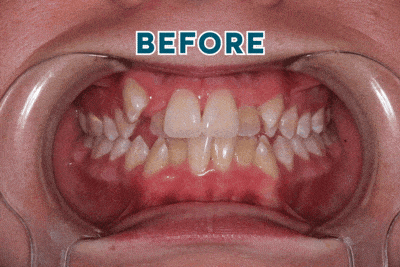

Case Study: Overcrowding & Misaligned Teeth Treatment

Creating Healthy, Balanced Smiles with Expert Orthodontic Care

Overcrowding and misaligned teeth can affect both the appearance of your smile and your overall oral health. At Smiles Orthodontics, we use modern orthodontic solutions to gently guide teeth into proper alignment. Correcting crowding not only improves the look of your smile but also makes it easier to keep your teeth clean and your bite functioning properly.